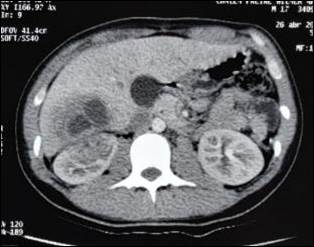

Al tercer día del tratamiento médico, presentó fiebre persistente que no cedía con antipiréticos, con presencia de aumento de leucocitosis (Glóbulos blancos 17 mil/mm3) a predominio de neutrófilos 92%, recabándose resultados de los cultivos periféricos: urocultivo negativo y hemocultivos periféricos con rescate de Pantoea sp. con resistencia probable a las betalactamasas, por lo cual se decide rotar antibiótico a imipenem y se solicitó nueva urotomografía simple y contraste endovenoso evidenciándose absceso renal e imagen abscedada en segmento VI hepático. (Figura 2)

Ilustración 2 UROTOMOGRAFÍA CONTRASTADO

Figura 1: Urotomografía. A) Simple: Se evidencia imagen hipodensa en polo superior de riñón derecho que se correlaciona con imagen hipodensa a nivel de lóbulo hepático derecho. B) Contrastado: En el segmento VI del lóbulo hepático derecho se evidencia una lesión ocupativa hipodensa tabicada con realce capsular periférico que mide 6,5 x 5 cm., está en contacto con el riñón, incluso en el parénquima renal se demuestra un área focal mediamente hipondesa compatible con absceso hepático con afectación al parénquima renal.